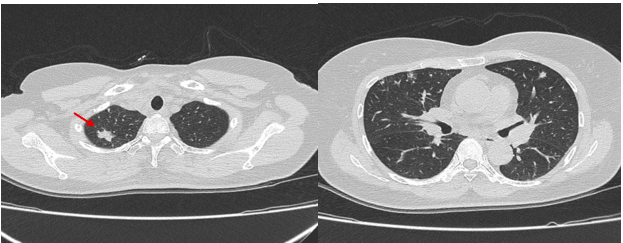

– Chụp cắt lớp vi tính lồng ngực: Nhu mô thùy trên phổi (Phải) có nốt tổn thương kích thước 13x14mm, bờ không đều, ngấm thuốc, sau tiêm. Rải rác nốt đặc 2 bên thùy phổi kích thước 3-10mm. Trung thất các nhóm 1R; 2R; 4R; 5; 8; 10RL có vài hạch lớn nhất kích thước 26x15mm; bờ không đều; ngấm thuốc không đồng nhất sau tiêm. Thượng đòn 2 bên có vài hạch tính chất tương tự; hạch bên phải kích thước 11x14mm

Hình 1. Hình ảnh cắt lớp vi tính ngực có tiêm: thùy trên phổi (P) có nốt tổn thương kích thước 13x14mm, bờ không đều, ngấm thuốc, sau tiêm. Nghi ngờ tổn thương nguyên phát (mũi tên đỏ)

– Cắt lớp vi tính lồng ngực: đám xẹp đông đặc đỉnh phổi phải kích thước 11mm; nhu mô phổi rải rác nốt đặc 5-10mm. Trung thất cân đối có vài hạch 10mm

Hình 6: Hình ảnh cắt lớp vi tính ngực có tiêm: đám xẹp đông đặc đỉnh phổi phải kích thước 11mm (mũi tên xanh nước biển)

Hình 7: Hình ảnh cắt lớp vi tính ngực có tiêm: Trung thất cân đối có vài hạch 10mm (mũi tên vàng). Hạch trung thất giảm kích thước rất nhiều chỉ sau 03 chu kỳ.

– Cắt lớp vi tính lồng ngực: Đám xẹp vùng đỉnh phổi phải, nốt đặc nhỏ kích thước 2-3mm. Không thấy hạch to hay khối trong trung thất

Hình 10: Hình ảnh cắt lớp vi tính ngực có tiêm: Đám xẹp vùng đỉnh phổi phải, nốt đặc nhỏ kích thước 2-3mm

Hình 11: Hình ảnh cắt lớp vi tính ngực có tiêm: Không thấy hạch to hay khối trong trung thất

| Các nốt đặc rải rác kích thước 3-10mm (mũi tên đỏ) (bên trái) đã biến mất | ||

| Tổn thương hạch trung thất bên trái (mũi tên vàng) đã biến mất | ||

Nhận xét: Chỉ sau 03 chu kỳ Pemetrexed – Carboplatin – Pembrolizumab, hình ảnh chụp cắt lớp vi tính cho thấy tổn thương phổi nguyên phát và các hạch giảm kích thước đáng kể. Đáp ứng điều trị được đánh giá là đáp ứng một phần theo tiêu chuẩn RECIST 1.1. Sau 9 chu Pemetrexed – Pembrolizumab, bệnh nhân tiếp tục ghi nhận cải thiện rõ rệt các triệu chứng lâm sàng, thể trạng ổn định, không xuất hiện tác dụng không mong muốn nghiêm trọng. Đánh giá trên hình ảnh chụp cắt lớp vi tính cho thấy tổn thương phổi nguyên phát tiếp tục giảm kích thước không ngấm thuốc chỉ còn là đám xơ xẹp vùng đỉnh phổi phải, các hạch trung thất và ngoại vi thu nhỏ rõ rệt, không phát hiện được trên phim chụp và không ghi nhận tổn thương di căn mới.